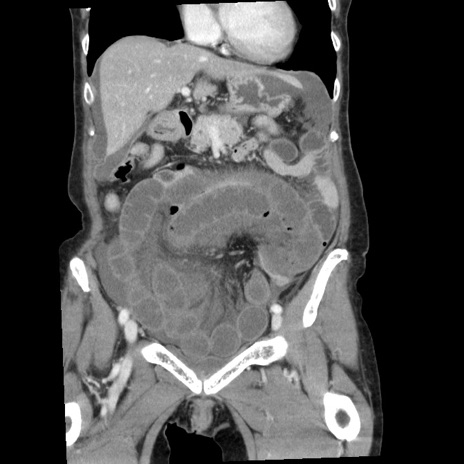

症例

【症例】80歳代女性

【主訴】腹痛

【現病歴】8時間前から腹痛あり来院。

【既往歴】糖尿病、脂質異常症、子宮体癌にて子宮全摘術

【身体所見】意識清明・会話良好だが腹痛で苦悶様、全腹部にわたって反跳痛と圧痛あり

【データ】WBC 13600、CRP 0.14、LDH 224、CK 90